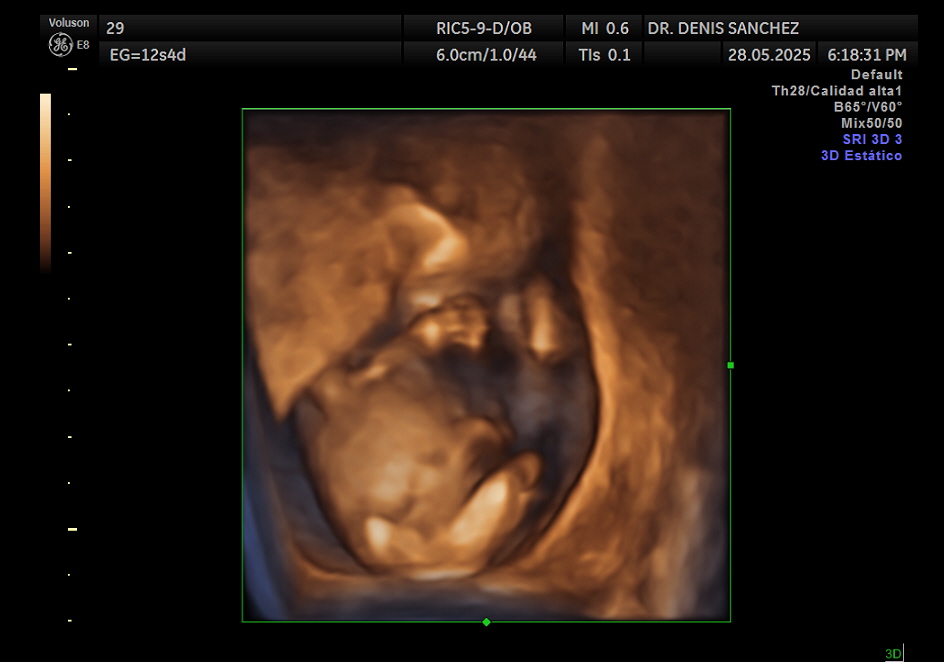

La ecografía cromosómica, también conocida como ecografía de tamizaje del primer trimestre, es una evaluación detallada que se realiza entre las 11 y 14 semanas de gestación. No analiza directamente los cromosomas, pero permite identificar marcadores ecográficos que podrían indicar un mayor riesgo de anomalías genéticas, como el síndrome de Down (trisomía 21), trisomía 18 o trisomía 13.

Determinar con exactitud la edad gestacional según la longitud céfalo-nalgas (CRL).

Este examen debe hacerse entre la semana 11 y 13 con 6 días, ya que es el período en el que los marcadores cromosómicos son evaluables con precisión. El momento ideal es cuando el bebé mide entre 45 y 84 mm de longitud céfalo-nalgas. Realizarlo fuera de este rango puede limitar la interpretación de los marcadores.

¿Qué se puede ver en una ecografía cromosómica?

Durante esta ecografía se observa:

Tamaño y forma general del bebé.

Frecuencia cardíaca fetal.

Marcadores de riesgo genético.

La anatomía básica del cráneo, columna, extremidades y órganos principales.

En muchos casos, una aproximación al sexo del bebé, aunque no sea definitiva.

Además, la ecografía puede detectar de forma temprana otras condiciones como hernias diafragmáticas, defectos de cierre del tubo neural o malformaciones mayores.